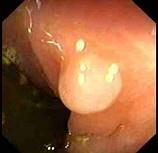

男性,46岁,有结肠癌家族史,行肠镜检查如图,诊断为 ( )A、直肠绒毛样息肉B、克罗恩病C、直肠炎性息肉D、直肠腺瘤样息肉E、直肠癌

问题 男性,46岁,有结肠癌家族史,行肠镜检查如图,诊断为 ( )

选项 A、直肠绒毛样息肉 B、克罗恩病 C、直肠炎性息肉 D、直肠腺瘤样息肉 E、直肠癌

答案 C